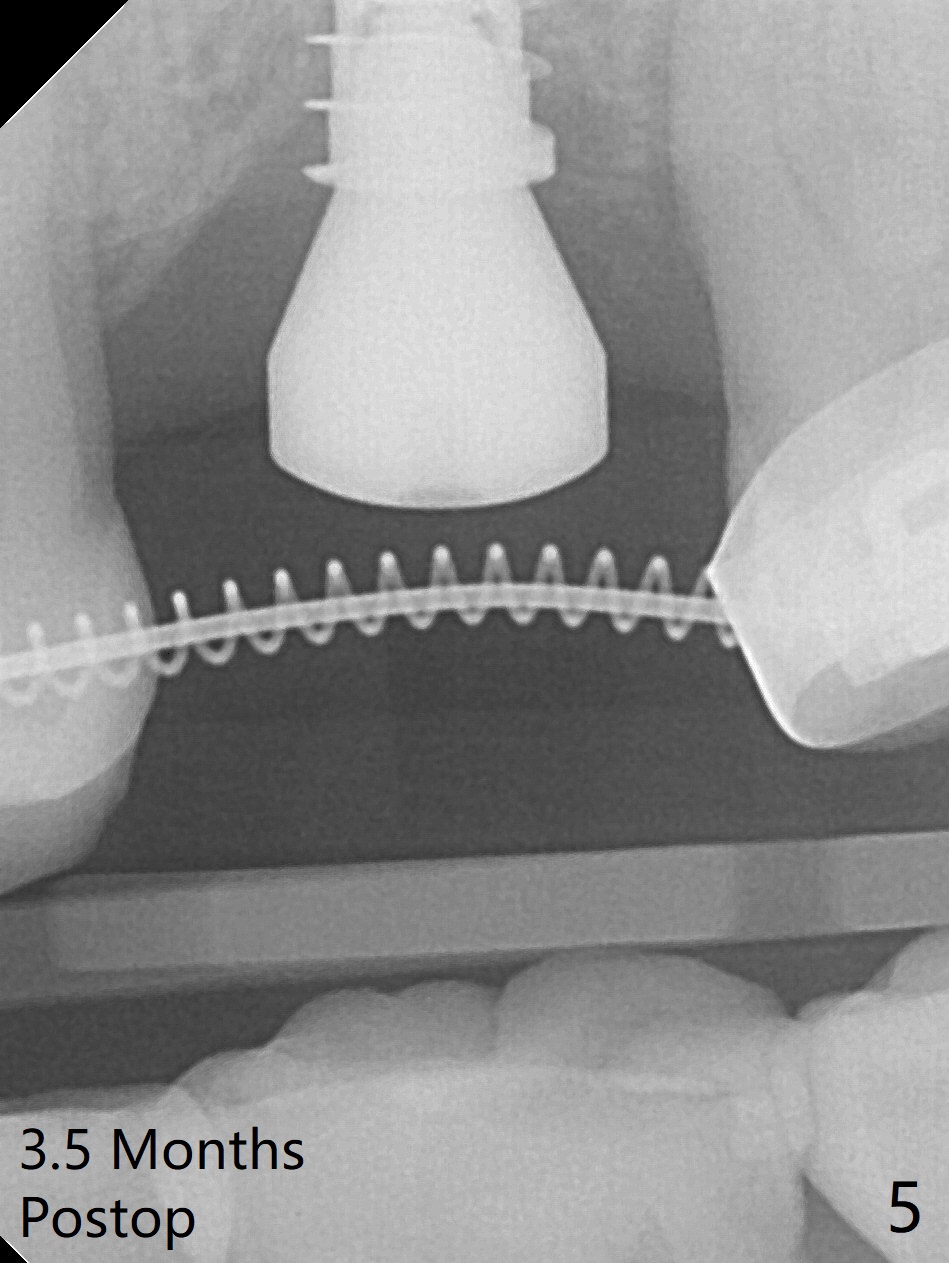

Preop exam shows the narrow ridge at #14. Magic split is used for access and initiation of osteotomy and bone expansion, followed by 3 mm Magic Expander for 11 mm (ME, Fig.1 (yellow line: sinus floor)). In fact the bone is soft. After use of 3.8 mm ME and Lindamann bur (to move the osteotomy distobuccally), a 4x11 mm dummy implant is placed with 20 Ncm (Fig.2). Following use of Lindamann bur for the same purpose as mentioned above, a 4.5x9 mm IBS implant is placed 3 mm subgingival with <30 Ncm (Fig.3,4). Bone graft is placed for sinus lift prior to implantation. A 5x3 mm healing abutment is placed. Bone loss is minimal 3.5 months postop (Fig.5) and striking 8 months postop (after crown cementation, Fig.6-8). The bone loss persists in spite of crown and abutment removal (Fig.9,10). Bone graft or implant redo is planned.